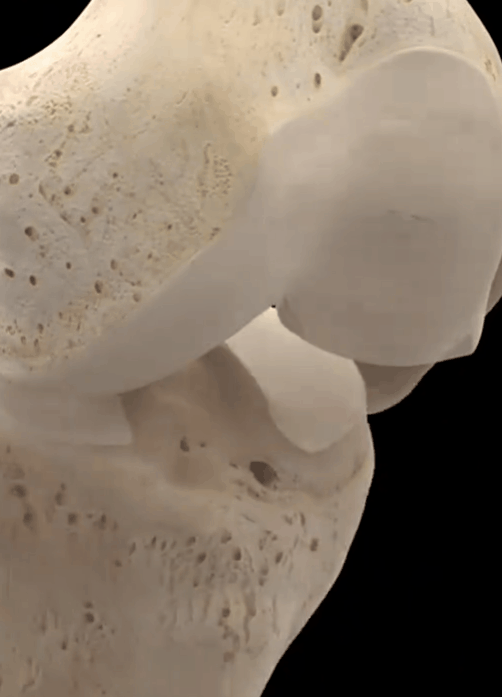

Comme vous pouvez le voir sur la photo ci-dessous, les articulations se sont typiquement développéesLacunes visibles, formation osseuse réduite, ostéoporose des articulations plus lourdesSi un tel patient présente des sensations et des douleurs anormales évidentes, l'injection intra-articulaire de vitrate de sodium ou l'administration constante d'analgésiques par voie orale le feront souffrir énormément, ce qui ne l'aidera pas vraiment à résoudre le problème.

Sur la surface des os de l'articulation du genou, il y a une couche de cartilage attachée, généralement dans l'articulation du genou sous une charge de pression excessive, ce sera à cause de l'usure du cartilage, dans nos activités, montrant la douleur ; l'usure du cartilage progressivement aggravée, conduira à l'os de la cuisse et l'os du mollet collision dure, la perte de la stabilité de l'articulation, et progressivement il y a ostéomalacie, la détérioration de la circulation sanguine, le refroidissement et le bruit d'éclatement est inévitable.

Dans les articulations du genou, la surface articulaire est recouverte d'un cartilage fin et lisse afin de permettre un mouvement suffisamment souple, et en cas d'usure due à une blessure ou à une surutilisation, la surface articulaire devient inégale, et l'os glisse sur la surface inégale pendant le mouvement de l'articulation, ce qui entraîne un bruit de cliquetis. Lorsque l'articulation bouge, l'os glisse sur la surface inégale de l'articulation et un bruit de cliquetis se produit, qui peut s'accompagner d'une douleur intense.